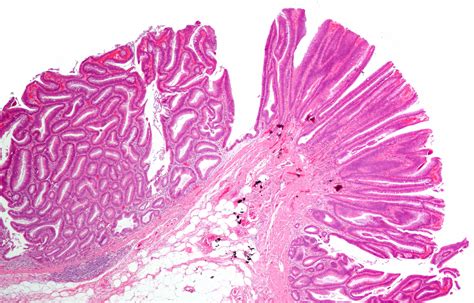

What is a Tubular Adenoma of the Colon?

A tubular adenoma is a type of polyp that forms on the inner lining of the colon. These polyps are composed of glandular tissue and are characterized by their tubular shape. Tubular adenomas are the most common type of adenomatous polyps, which are known to have the potential to become malignant if left untreated. Early detection and removal of these polyps are essential for preventing the development of colorectal cancer.